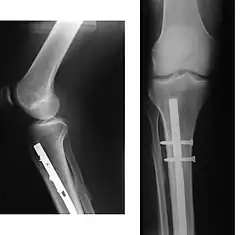

Periprosthetic fracture of left femur

In orthopedic medicine, fractures are classified in various ways. Historically, they are named after the physician who first described the fracture conditions; however, there are more systematic classifications as well.

• Periprosthetic fracture – a fracture at the point of mechanical weakness at the end of an implant.

X-ray showing the proximal portion of a fractured tibia with an intramedullary nail